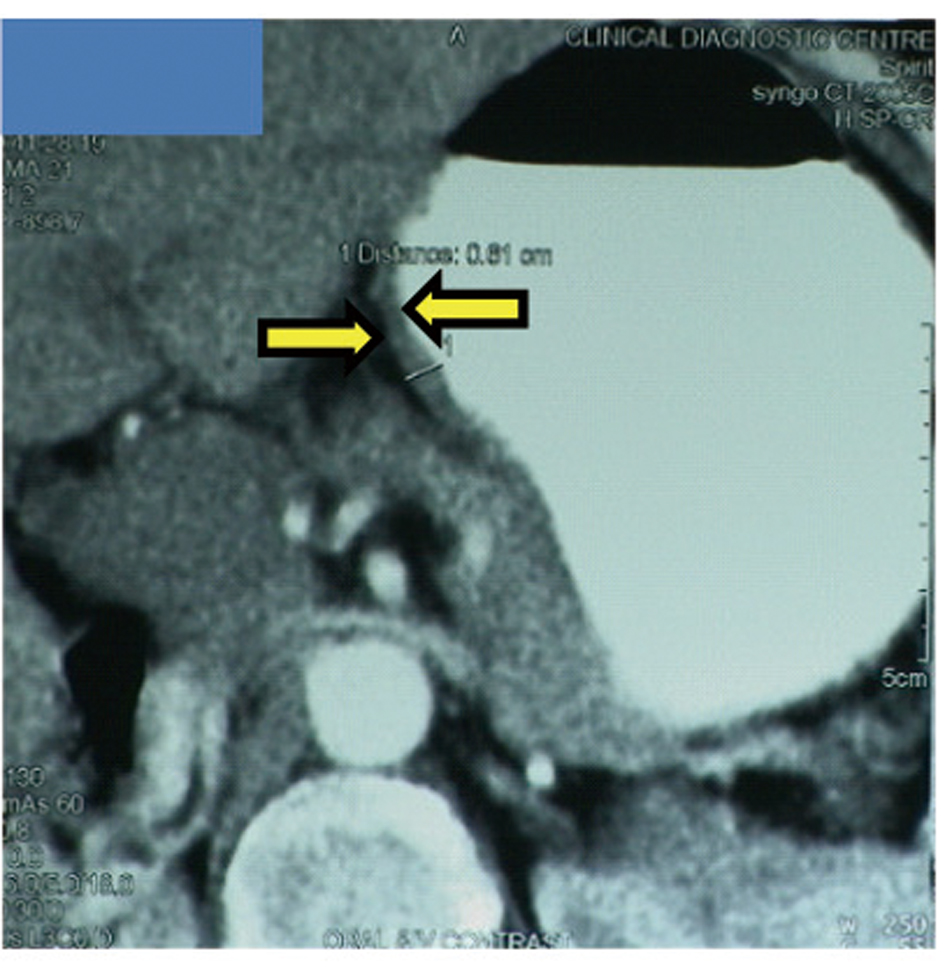

A 65-year-old postmenopausal woman presented in May 2007 with vomiting, early satiety and 20 lbs weight loss over last 2 months. There was no history of associated fever, cough, bleeding from any site, and the family history was also insignificant. On examination, pallor was present. However, no icterus, edema or lymphadenopathy was noted. Detailed systemic examination revealed no abnormality. Investigations revealed mild anemia (Hb 9.8 g/dL) and elevated alkaline phosphatase levels (310 U/L). Esophagogastroduodenoscopy (EGD) showed large ulcerated lesion at the fundus, extending into the esophagus. CECT abdomen showed mass lesion in gastric cardia extending to involve the gastroesophageal junction and fundus, with compression of fat planes and wall thickness of 44 mm. There were multiple space occupying lesions (SOLs) in the right lobe of liver, the largest measuring 4.3 x 3.1 cm (Fig. 1). Tissue specimens from endoscopic biopsy (gastric region) and CT guided FNAC of liver showed moderately differentiated adenocarcinoma. Hence, a diagnosis of gastric carcinoma with liver metastases was made. Tumor markers - CEA and CA 72.4 levels were 1.7ng/mL and 0.99 U/mL respectively. The patient was then started on chemotherapy regimen consisting of docetaxel, oxaliplatin and capecitabine (DOX). Docetaxel was administered as 25 mg/m2 followed by oxaliplatin 50 mg/m2 on days 1 and 8, with capecitabine 625 mg/m2 BID from days 1 to 14, in 21-day cycles. The protocol was well tolerated by the patient except for grade 2 hematologic toxicity, which responded to blood product transfusions, erythropoietin and G-CSF. Patient also experienced diarrhea, managed with supportive therapy. A thorough workup done was after 3 and 6 cycles of chemotherapy to evaluate the response. Investigations at the end of 6 cycles of chemotherapy (November 2007) showed decreased gastric lesion, with a wall thickness of 8 mm on CT abdomen (Fig. 2); the particular liver lesion also decreased in size to 1.3 x 1.1 cm. EGD revealed few small erosions in fundus near the gastroesophageal junction, no ulcer or growth was seen. CT abdomen done 3 months later (February 2008) showed complete absence of gastric and liver lesions (Fig. 3). This patient responded dramatically to the chemotherapy protocol, as evidenced by > 50% decrease in the size of gastric and liver lesions after 6 cycles of chemotherapy, and complete disappearance of the lesions after further 3 months. Hence the patient’s clinical response to chemotherapy was labeled as CR. The patient continued to maintain CR for about 9 months, since the initial response.

![]() Click for large image | Figure 1. Disease status at the time of diagnosis. Gastric cancer with gastric wall thickness of 44 mm (left), Liver metastases (right). |